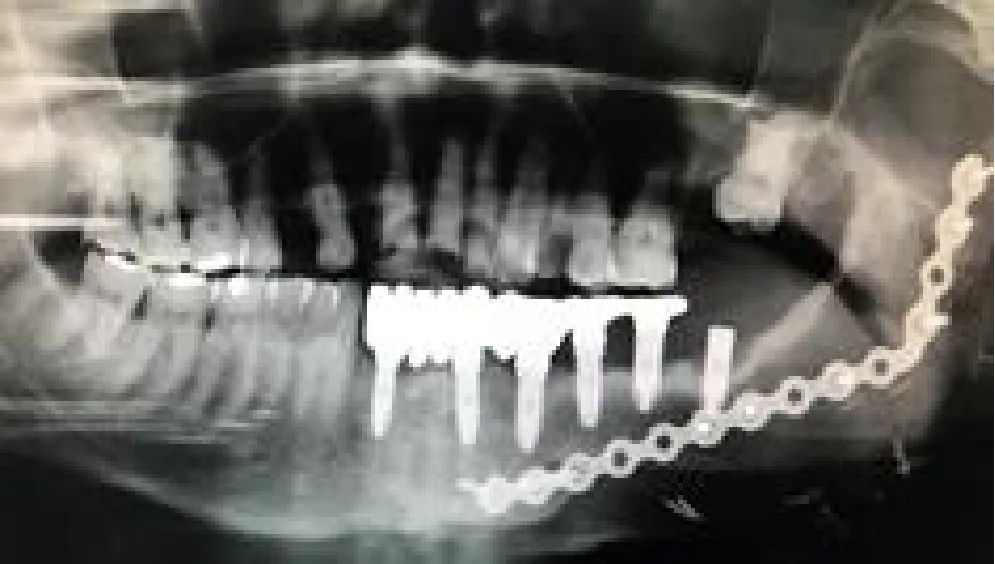

| Mandibular right body and ramus ameloblastoma | Segmental mandibulectomy | Fibula flap | sCAIS | 2 flap, 1 failed | Fixed screw retained | ![]() |

| Right mandibular body epidermoid carcinoma | Segmental mandibulectomy and neck dissection | Double-barrel fibula flap | dCAIS | 3 flap | Fixed screw retained | ![]() |

| Left mandibular body epidermoid carcinoma | Segmental mandibulectomy and Neck dissection | Iliac crest free flap | dCAIS | 2 flap | Fixed screw retained | ![]() |

| Left mandibular body ameloblastoma | Segmental mandibulectomy | Fibula flap | dCAIS | 4 flap | Fixed screw retained | ![]() |

| Right mandibular body ameloblastoma | Segmental mandibulectomy | Fibula flap | dCAIS and freehand | 3 flap | Fixed screw retained | ![]() |

| Hard palate adenoid cystic carcinoma | Central maxillectomy | Radial forearm flap | dCAIS and sCAIS | 5 Mx | Fixed screw retained | ![]() |

| Left maxilla tuberosity adenocarcinoma | IIb Brown maxillectomy | Iliac crest free flap | dCAIS and sCAIS | 3 flap | Fixed screw retained | ![]() |

| Left mandibular body epidermoid carcinoma | Segmental mandibulectomy and Neck dissection | Double-barrel fibula flap + 70 Gy | dCAIS and sCAIS | 3 flap | Fixed screw retained (Pending) | ![]() |

| Left mandibular body epidermoide carcinoma | Segmental mandibulectomy and Neck dissection | Fibula flap | dCAIS and sCAIS | 3 flap | Fixed screw retained (pending) | ![]() |

| Right hemitongue epidermoid carcinoma | Hemiglosectomy, bilateral neck dissection | Alt+ Vastus Lateralis Flap + 70 Gy | dCAIS | 6 mx | Fixed screw retained (pending) | ![]() |

| Left hemimandible ameloblastoma | Segmental mandibulectomy | Failed Fibula flap and pectoralis major | sCAIS | 5 mx | Fixed screw retained (pending) | ![]() |